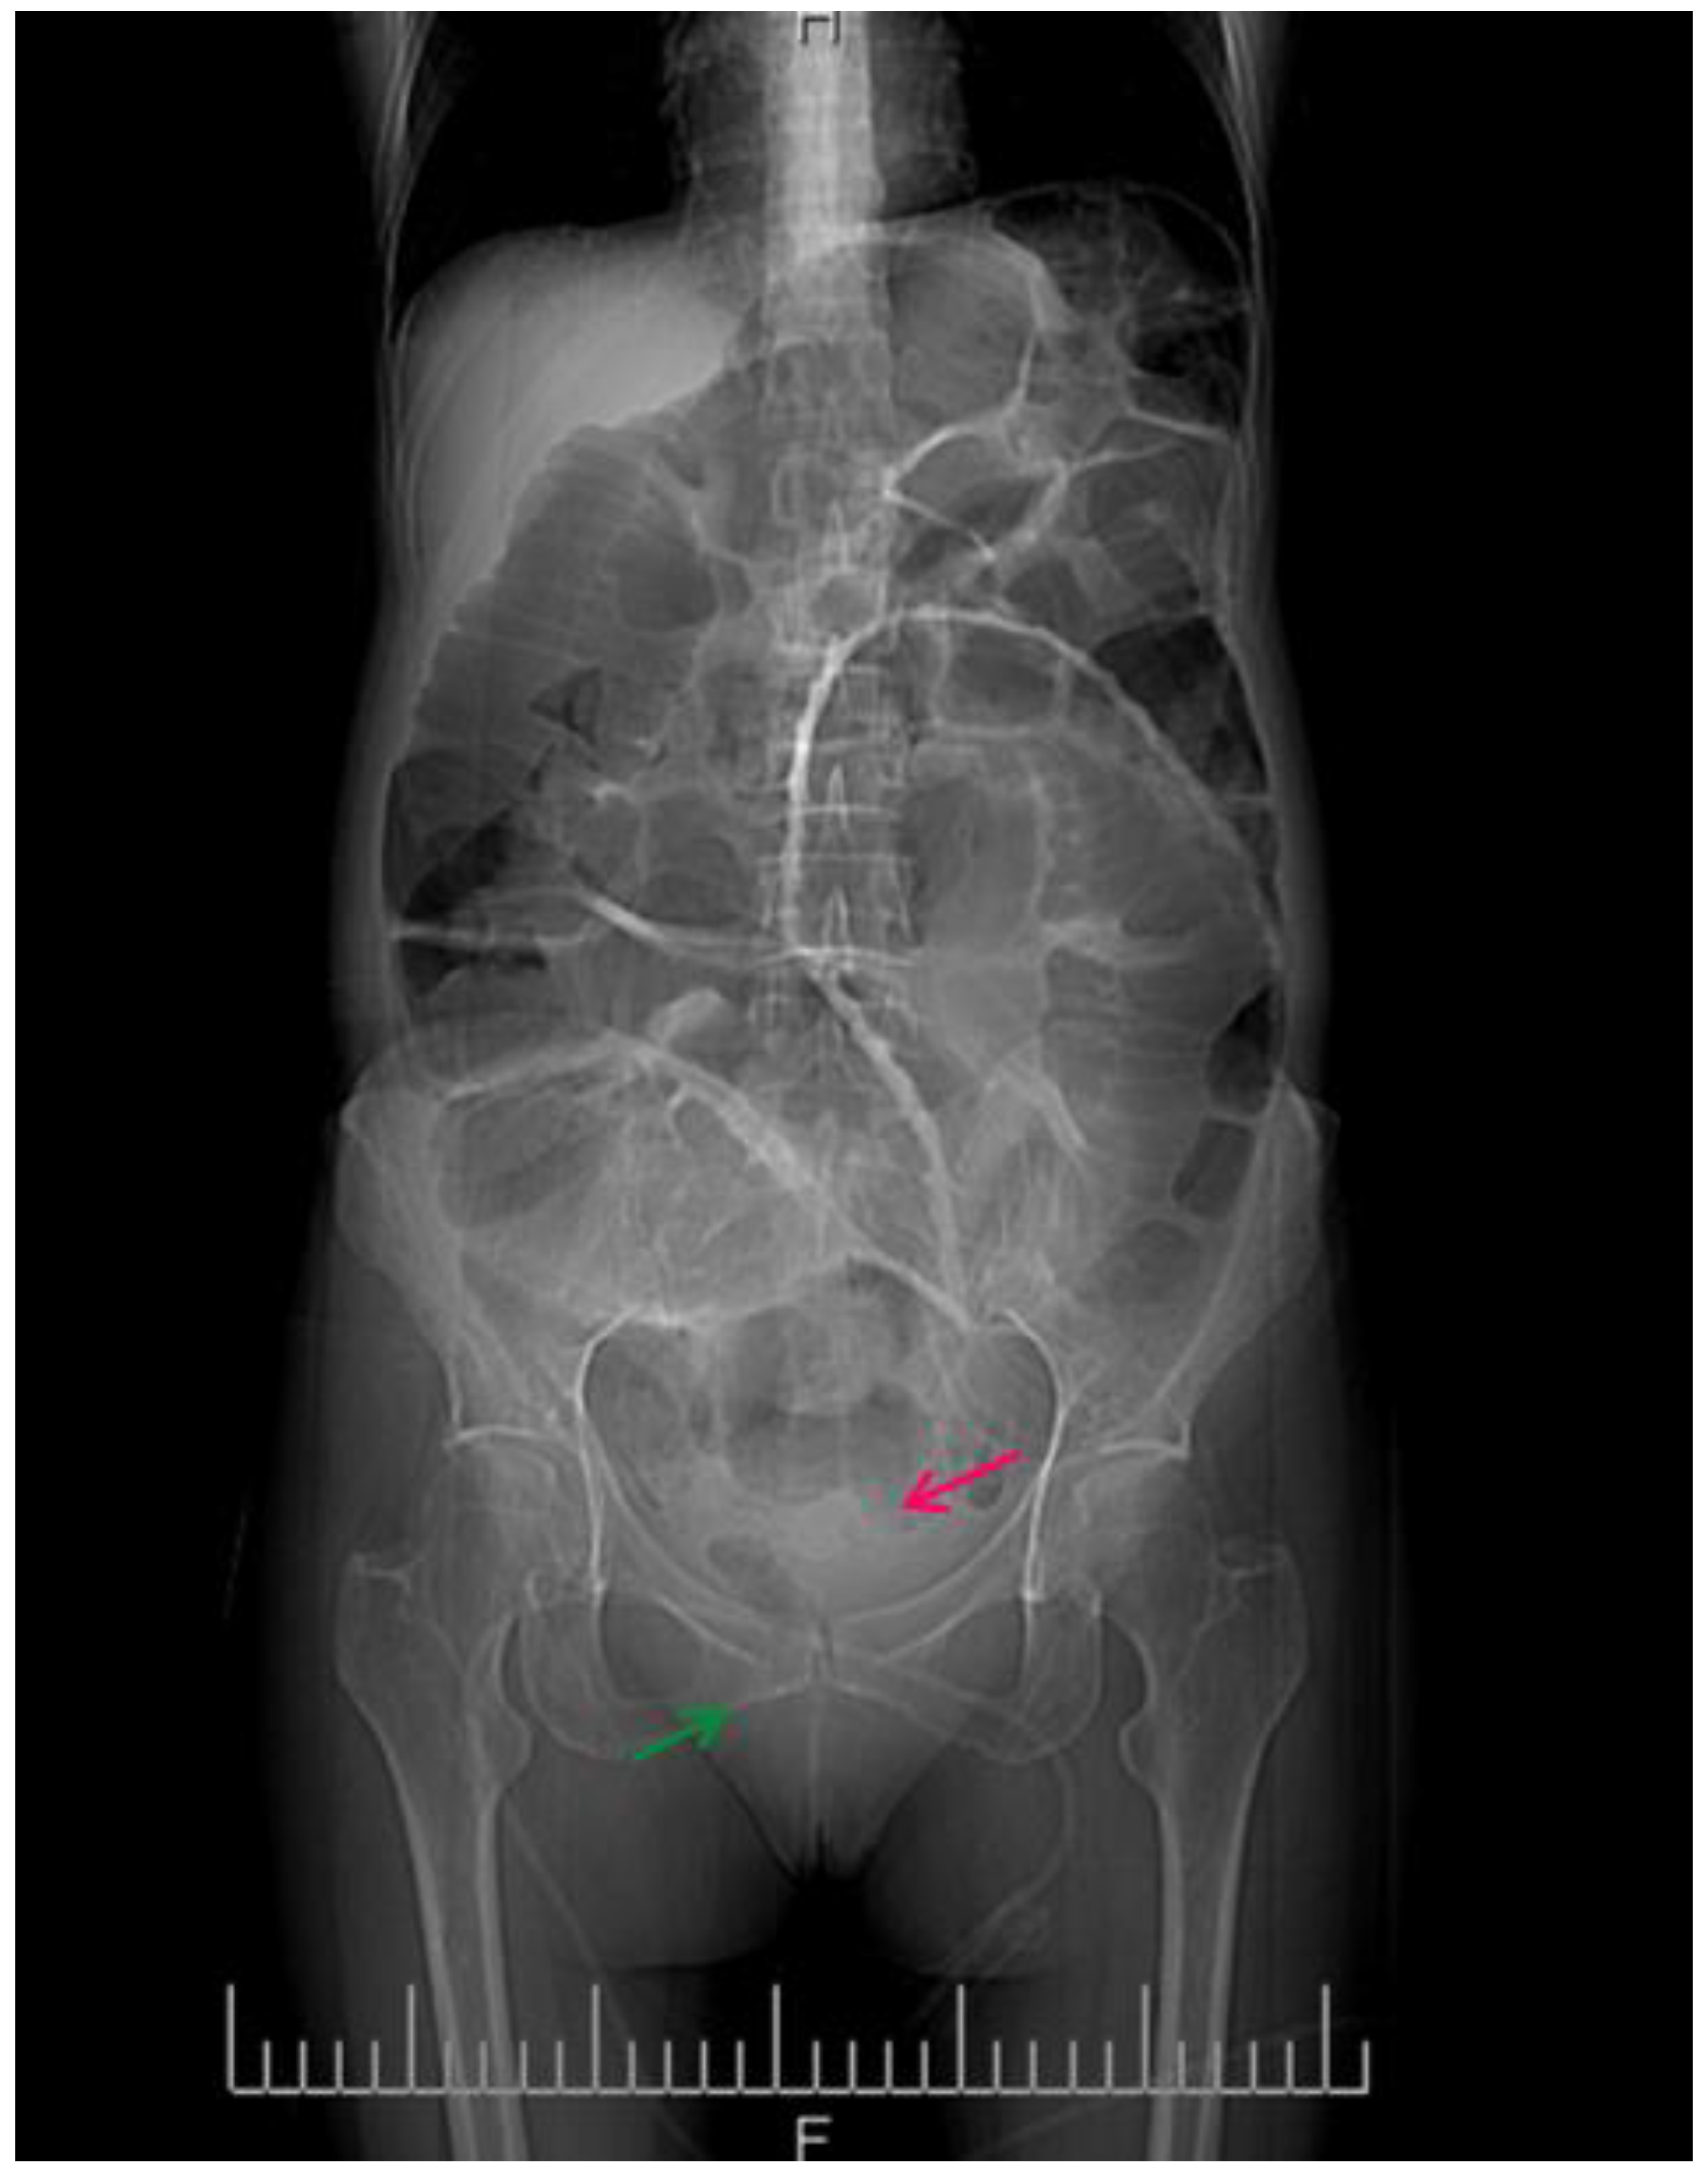

Figure 3 shows the contrast-enhanced CT scan of the abdomen and pelvis being performed, which provided a detailed view of the abdominal cavity.

Figure 3.

CT image of the intestinal volvulus—“whirlpool sign” (red arrow), air loops (green arrow).

This abdominal X-ray shows multiple dilated loops of the small bowel with prominent air–fluid levels, a classic radiographic feature indicative of bowel obstruction. The image reveals significant distension of the bowel loops, which are visibly outlined by the accumulated air and fluid, highlighting the extent of the obstruction. The presence of these air–fluid levels is a critical diagnostic sign, suggesting that the bowel segments are filled with both air and liquid, which occurs when there is a blockage preventing the normal passage of intestinal contents. The upright position of the X-ray allows for a clear visualization of these levels, helping in the confirmation of the diagnosis.

Figure 4 below shows multiple dilated loops of the small bowel with air.

Figure 4.

CT image of multiple dilated loops of small bowel with air (red arrows), and fluid (green arrow).

This distension is seen in many cases of small bowel obstruction, leading to the buildup of gas and fluid in the proximal segments. The absence of air in the distal bowel segments further supports the diagnosis of obstruction.